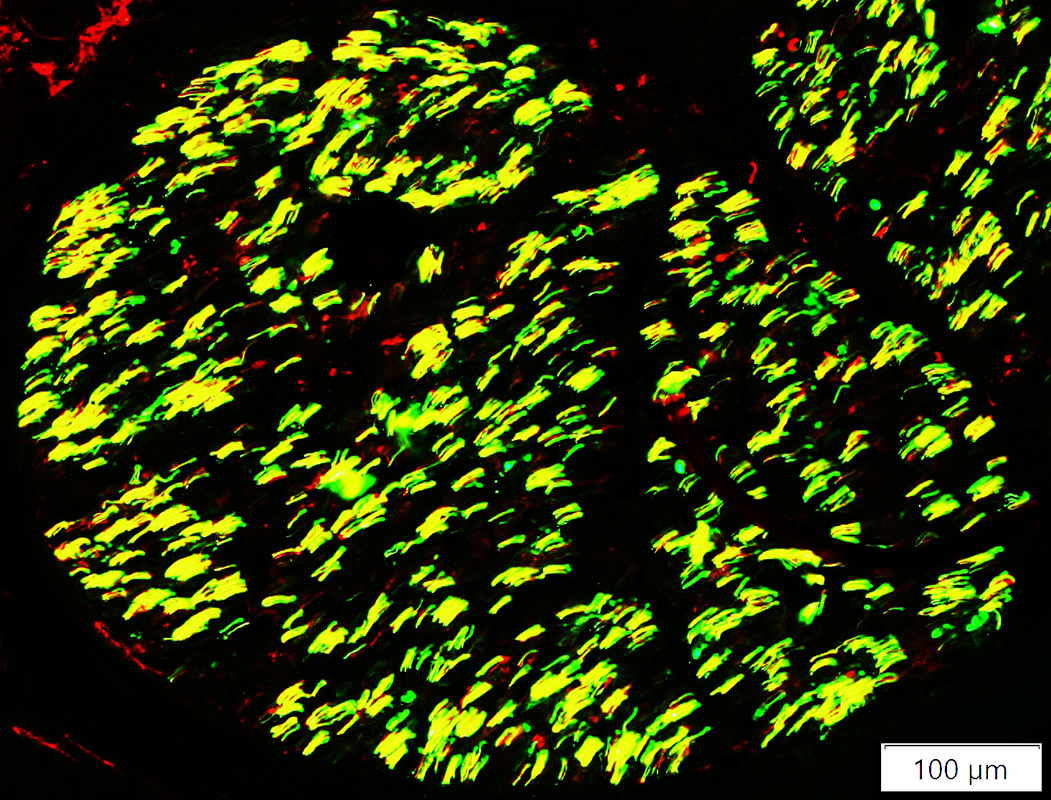

Neurofilament (Green), Myelin basic protein (Red) stain

Neurofilament stained axons in sural nerve (Yellow)

Lost within many MBP stained myelin sheaths (Red)

Unmyelinated Axons: preserved numbers (Green)